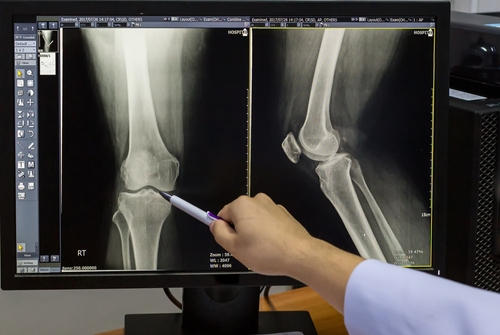

Фотогалерея